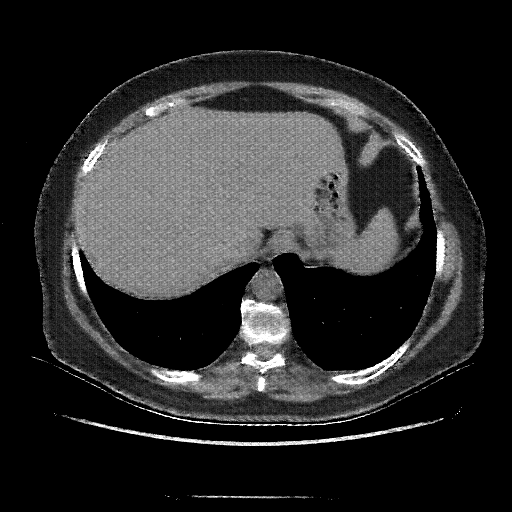

Reconstructed NATIVE CT scan (cycle consistency)

Full window (WL 1023.5, WW 4095 β†’ Low βˆ’1024, High +3071)